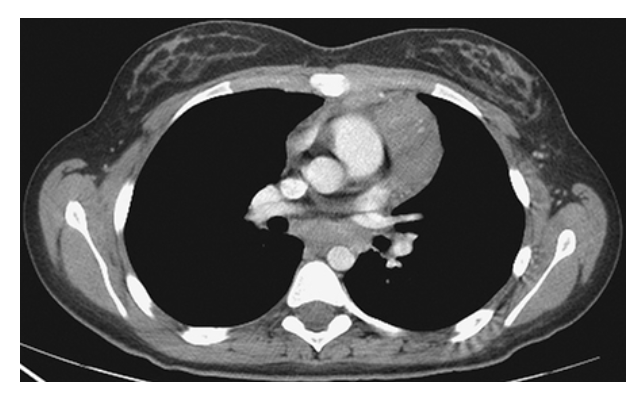

What is A

Thymoma. Axial coronal MPR

What is B

Thymoma. Axial and sagittal MPR

What is C

Thymoma. Axial CECT images show a large lobulated mass within the left anterior mediastinum. This was found to be a mixed lymphoepithelial thymoma at surgery.